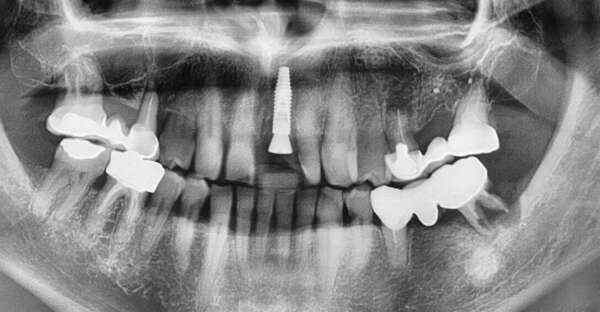

Un patient de 60 ans est venu consulter pour une mobilité d'une incisive centrale maxillaire.

Cette dent sera extraite l'implant sera posé dans la même séance et la pose de la couronne provisoire sera faite dans les 4 heures.

Cas réalisé par le Dr Bernard Gounel et le laboratoire Alliance Prothèse.